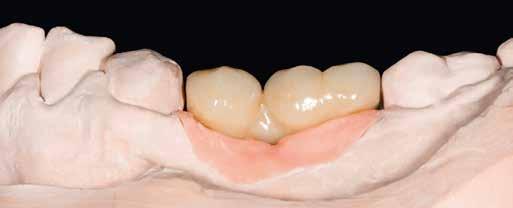

Interdiszciplináris fogászati kezelés myofunkcionális készülék, alignerek és protetikai ellátás alkalmazásával

MED. DENT Abradált frontfogakkal rendelkező felnőtt páciens interdiszciplináris kezelése